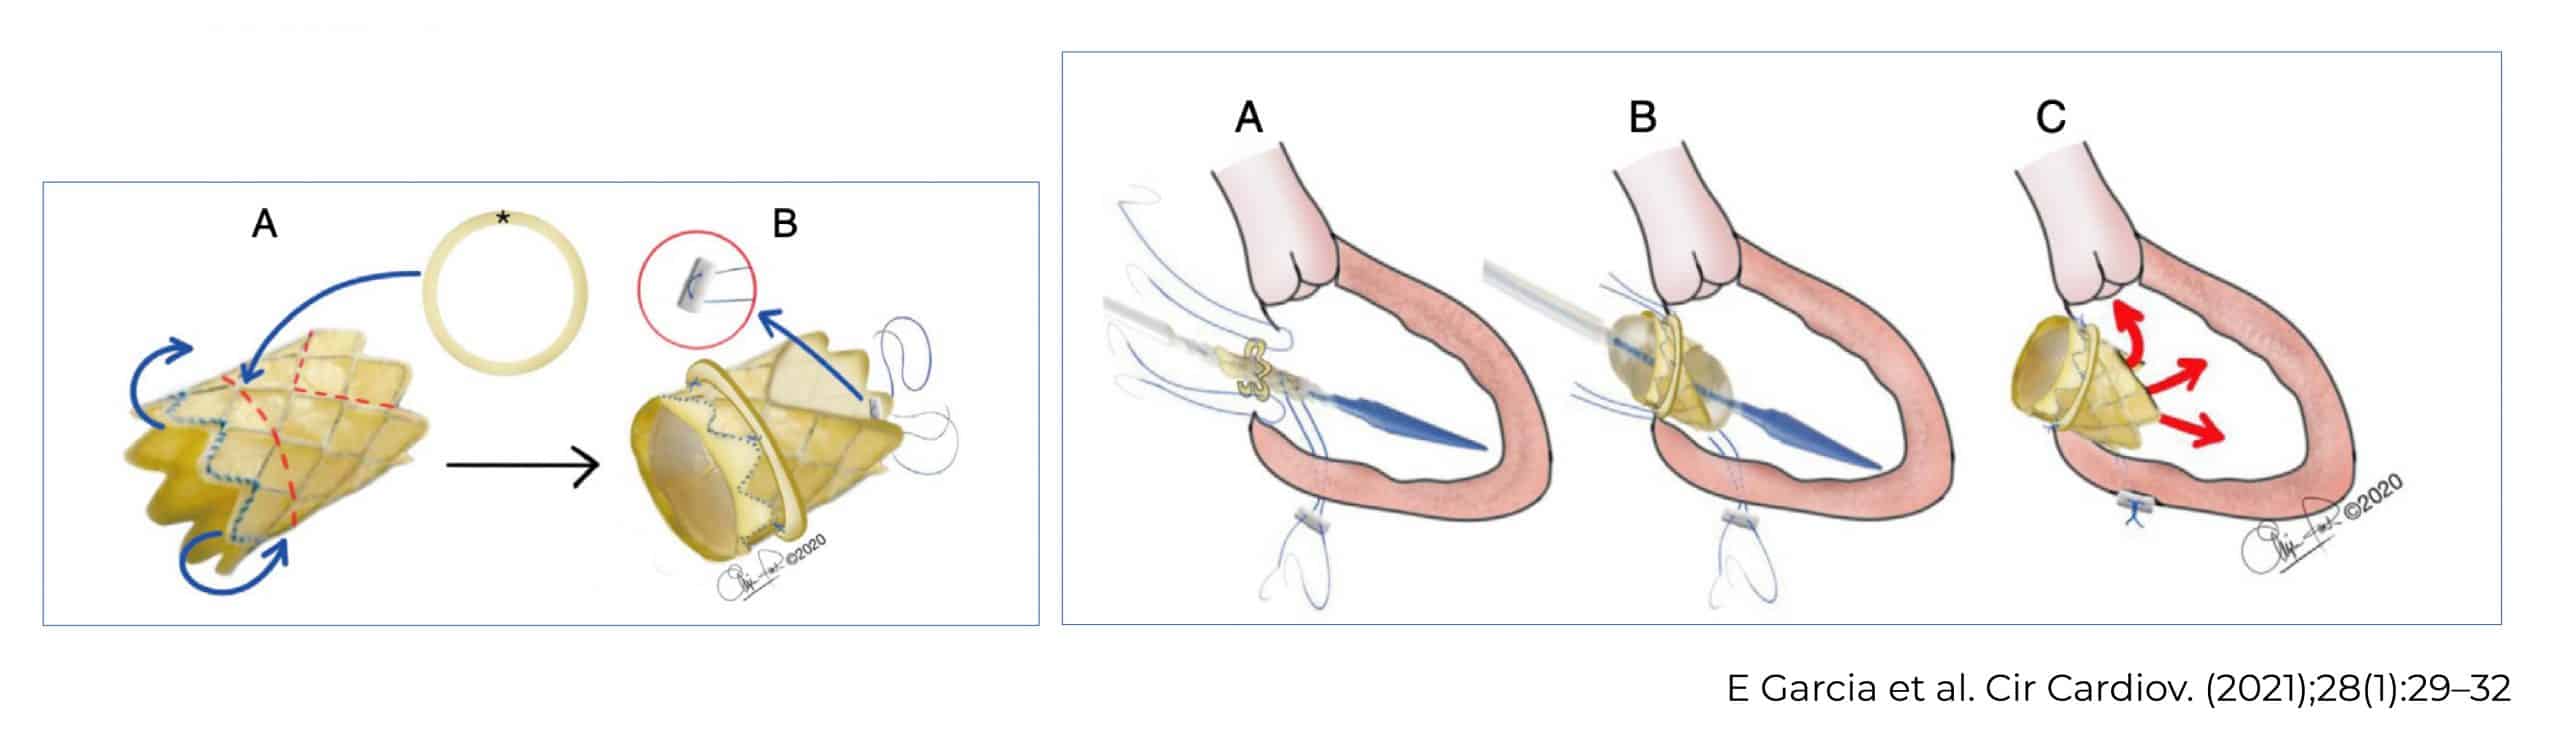

Cirugía de Ross-Konno

La cirugía de Ross-Konno permite reparar la válvula aórtica dañada. Para ello, se utiliza la válvula pulmonar en posición aortica con translocación de las coronarias y en posición pulmonar se colocó un conducto contegra.

Además, debido a la doble lesión mitral con insuficiencia grave, también se colocó una válvula Melody® en posición mitral; y se realizó una resección de fibroelastosis.